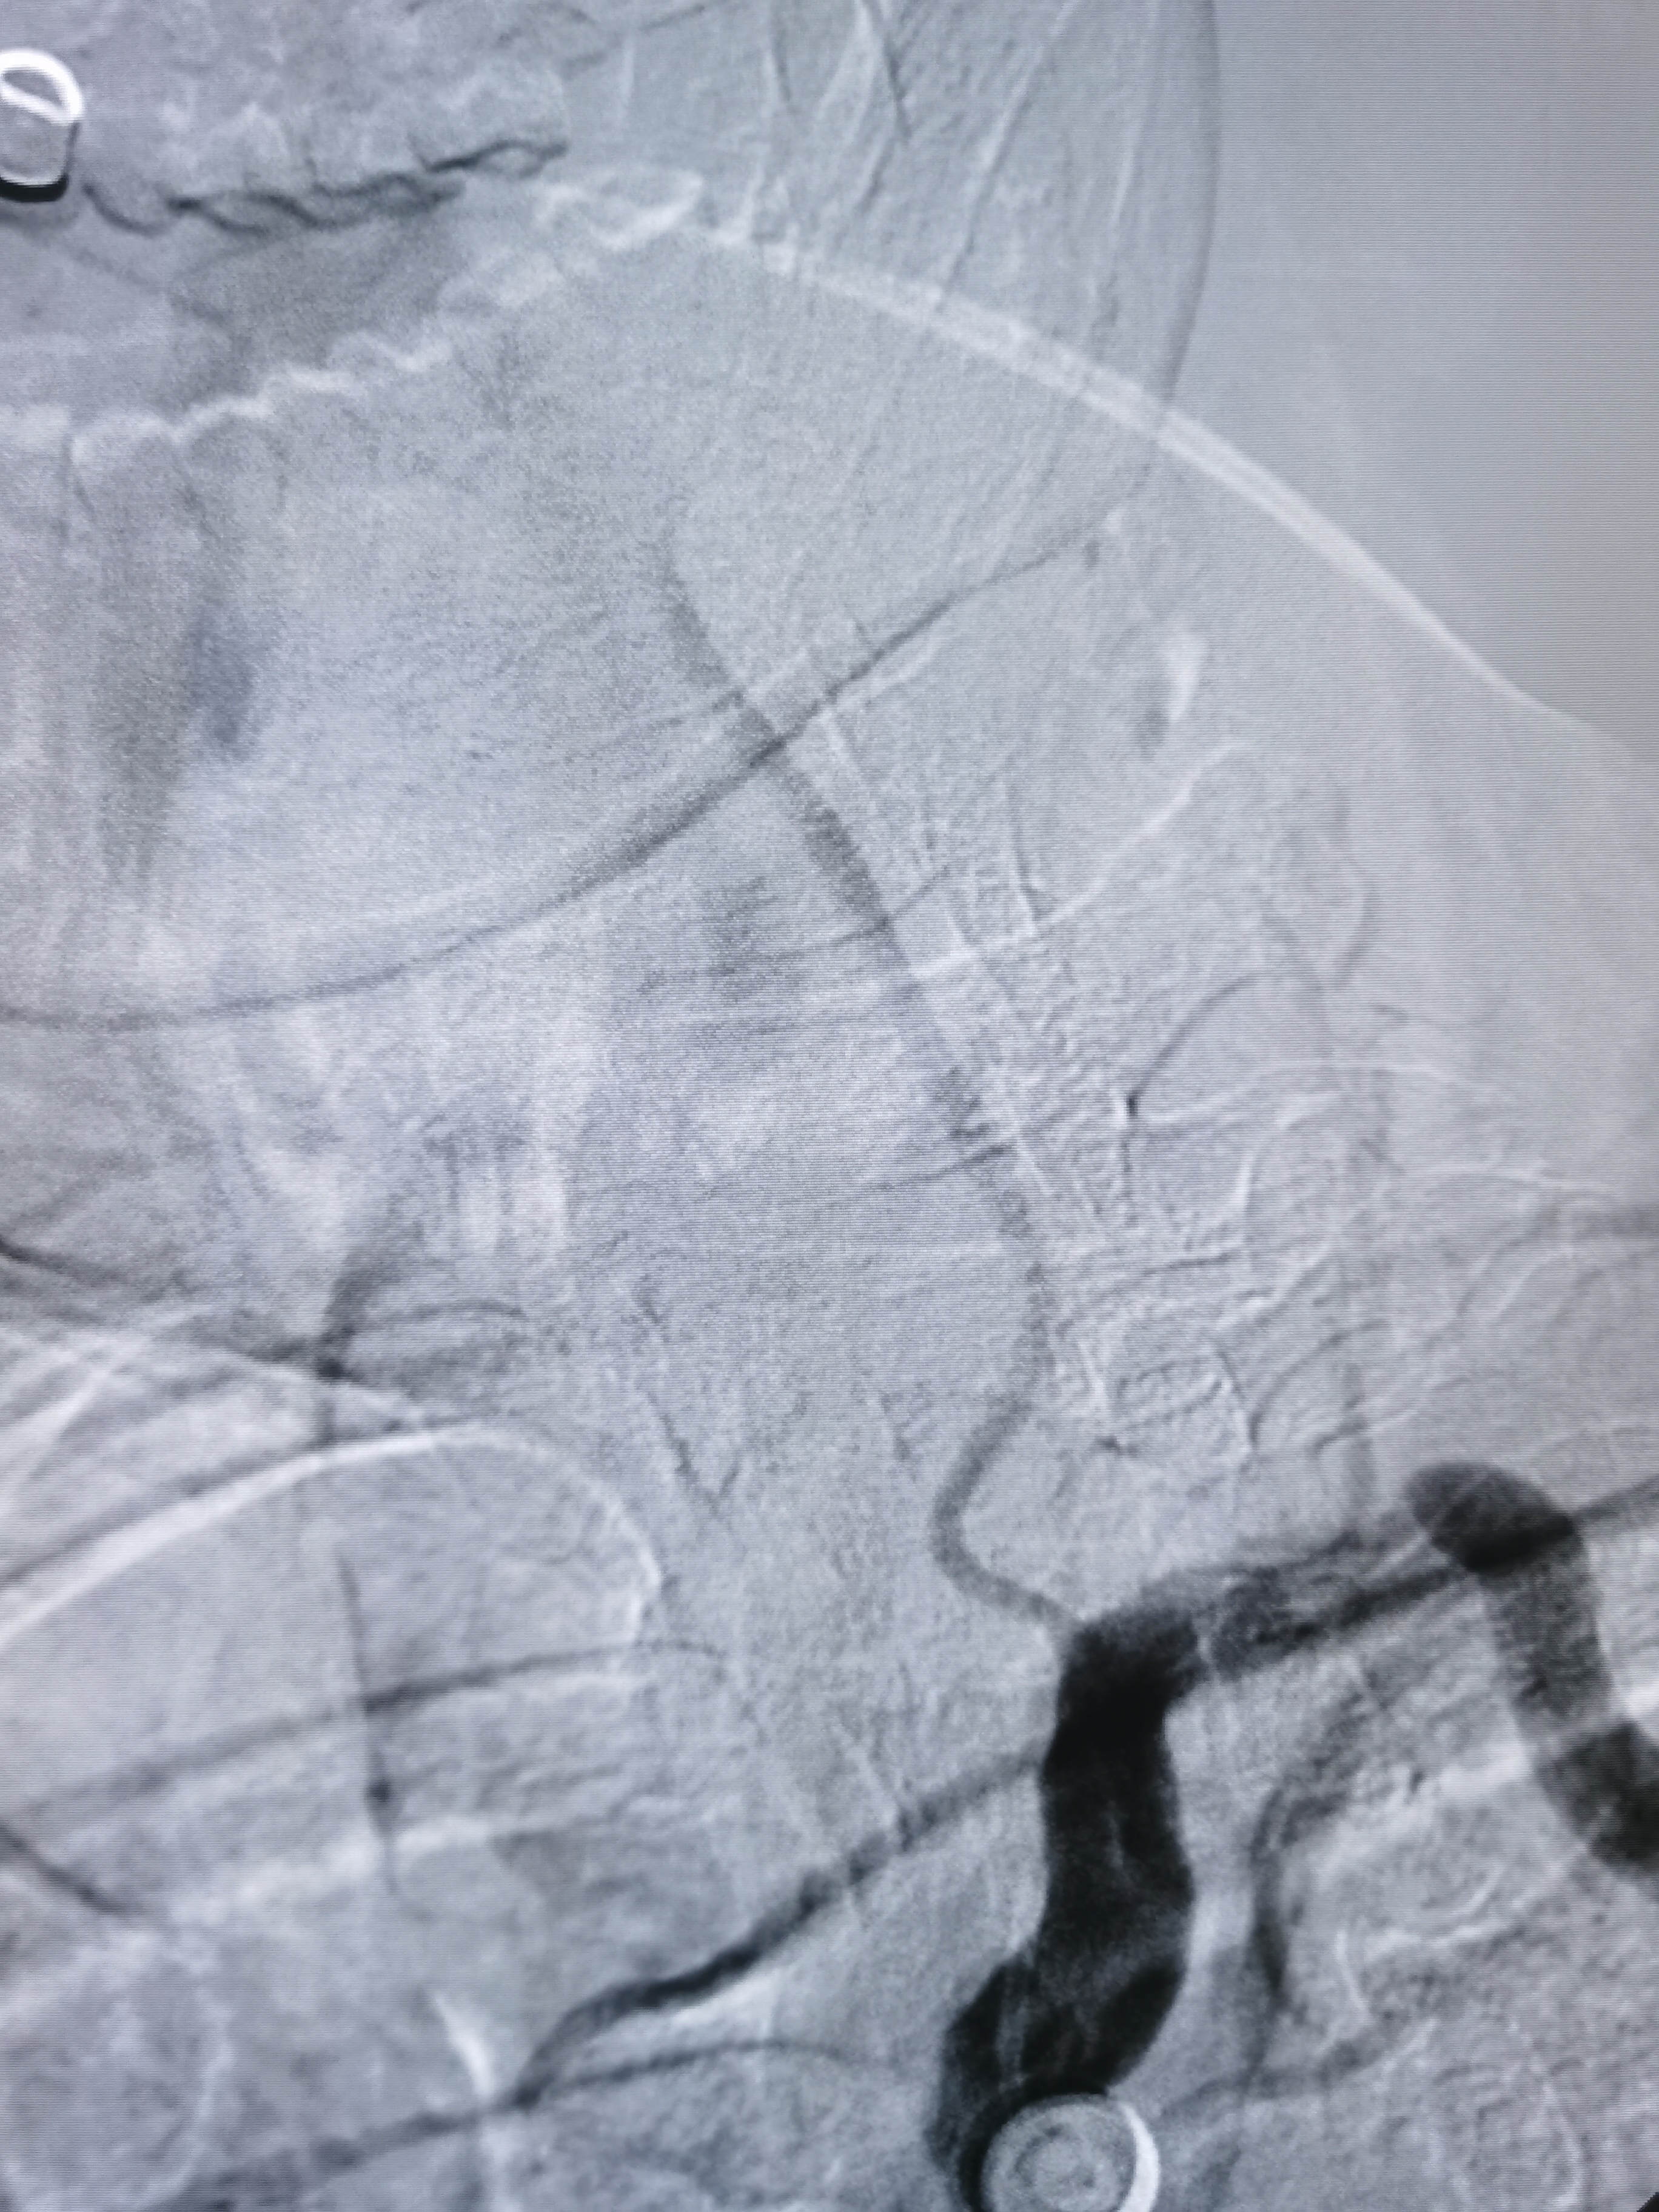

支架位置形态满意,撤出保护伞,结束手术。

术前术后对比